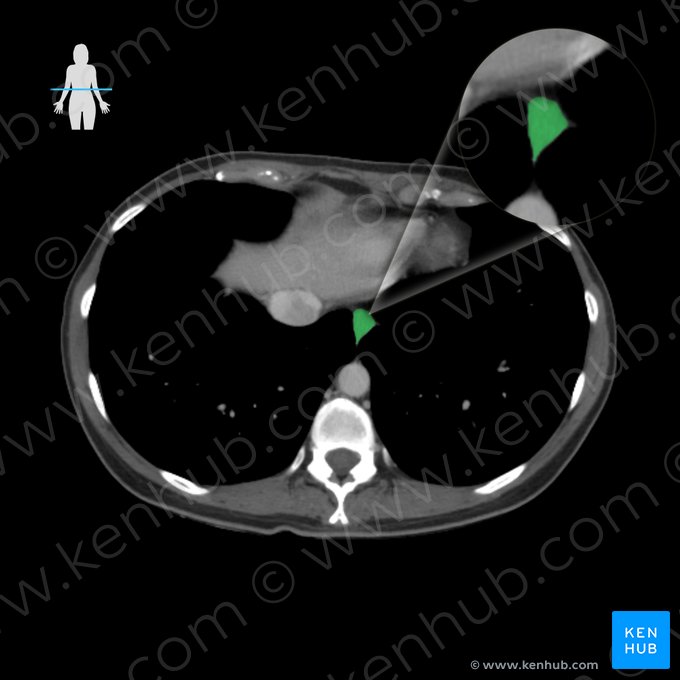

- Uma TC ou RNM abdominais são métodos de imagem que podem ser realizados em alguns casos, quando houver suspeita de outras doenças.